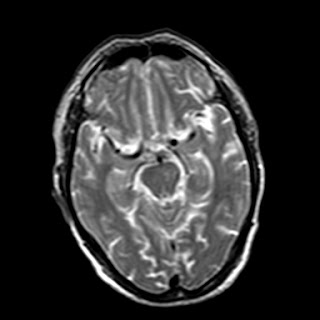

39 years old man with chronic alcoholic since 17 years.

& cough with cold & dark colour stool.

Now feeling weakness & dimness of vision.

O/E images: